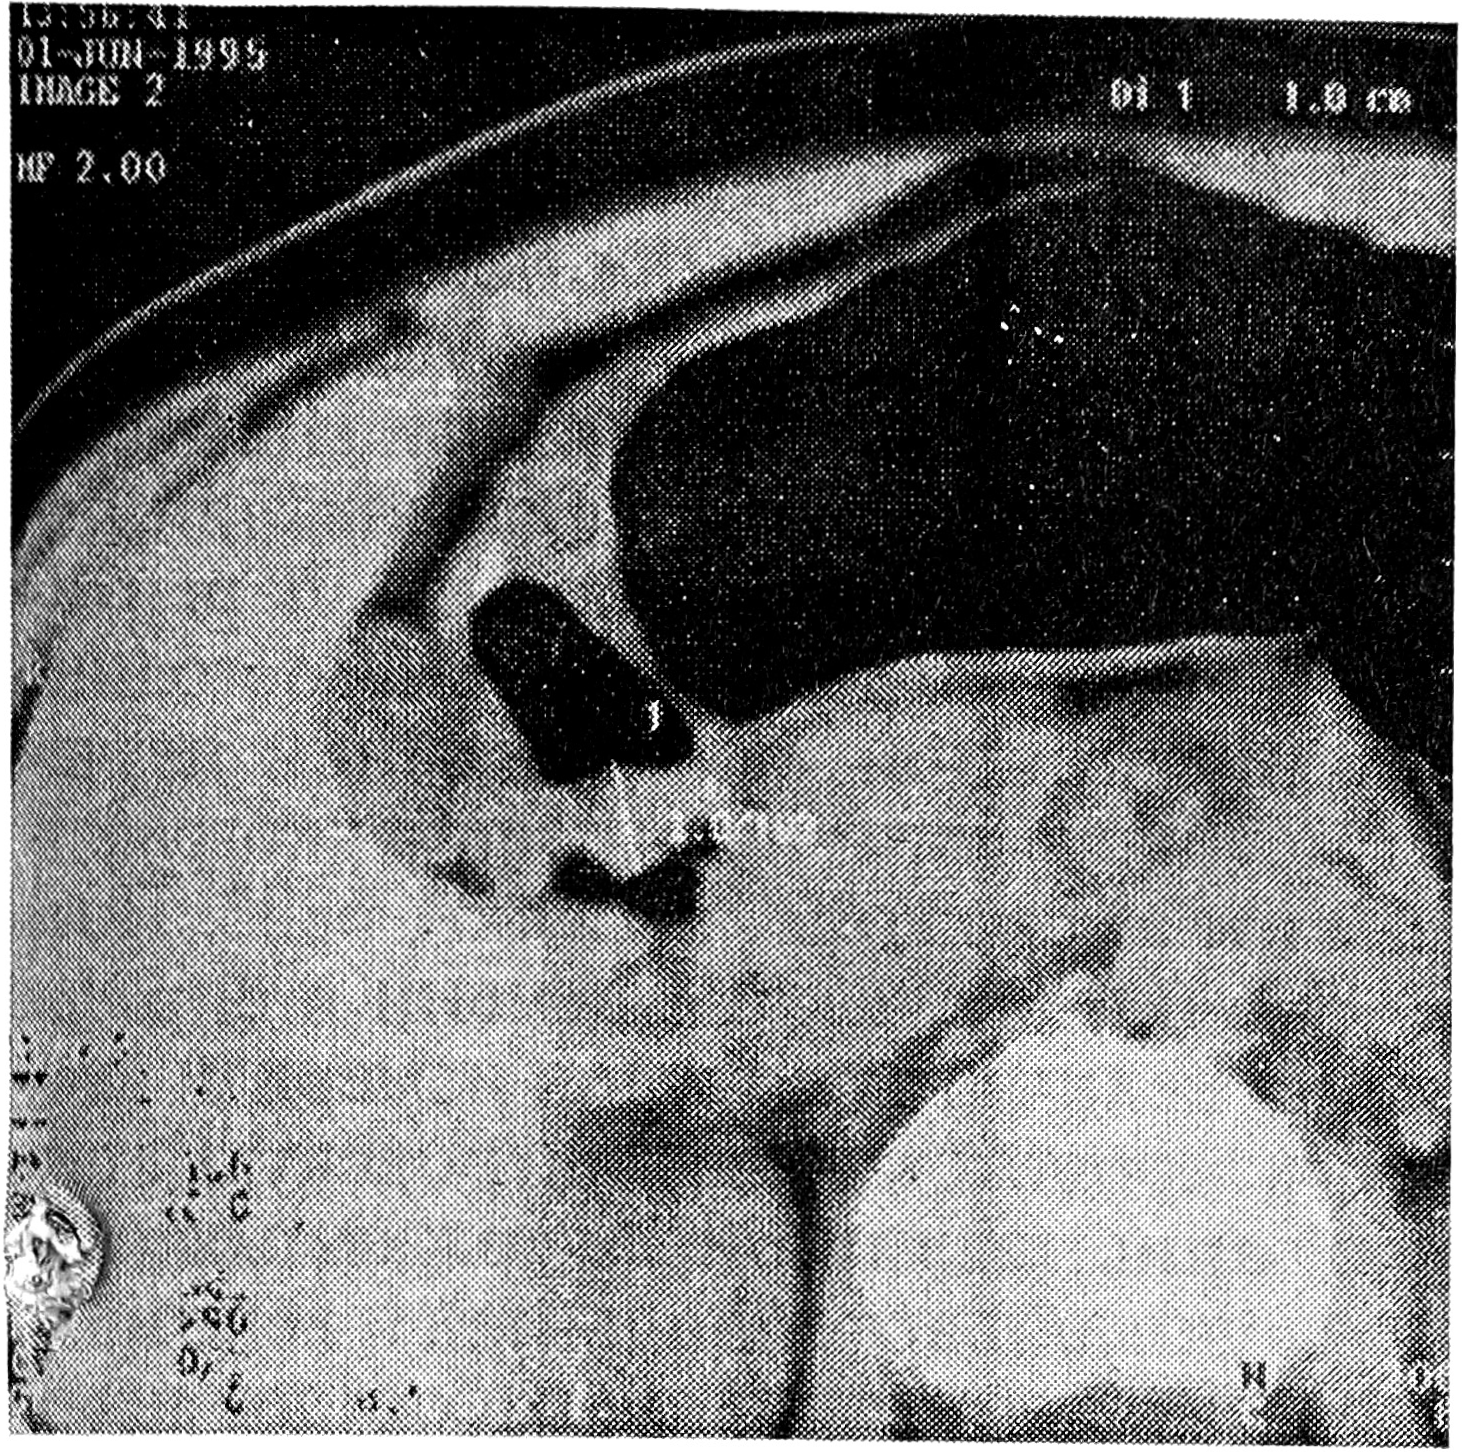

Исследование показало, что основным КТ-признаком эндофитного рака желудка можно считать утолщение его стенки в месте опухолевого поражения до 1 см и более (рис. 1). При опухолях небольших размеров (до 4-5 см) это утолщение носило локальный, ограниченный характер. Распространения процесса за пределы стенки желудка на соседние структуры не наблюдалось. Контур поражения был ровный, эластичность стенки нарушалась незначительно (рис. 2, 3). Отчетливую границу между пораженным участком и неизмененной стенкой желудка провести было трудно. При КТ-диагностике сравнительно небольших по размерам эндофитных опухолей желудка (вызывающих затруднения как при классическом рентгенологическом, так и при эндоскопическом исследованиях) необходимым условием являлась сравнительная оценка толщины стенки желудка на ограниченных участках с соседними неизмененными участками. Даже незначительное утолщение ограниченного участка стенки (до 7-8 см) при наличии других рентгено-эндоскопических признаков эндофитного поражения являлось дополнительным критерием, подтверждавшим эндофитный рак желудка. К достоинствам КТ необходимо отнести возможность обнаружения в процессе исследования гионарных и отдаленных метастазов, которые встречались достаточно часто даже при небольших по размерам опухолях желудка.

Рис. 3. КТ желудка больной К., 29 лет. Небольшой эндофитный рак препилорического отдела. Определяется ограниченное утолщение задней стенки препилорического отдела желудка до 1,0 см.